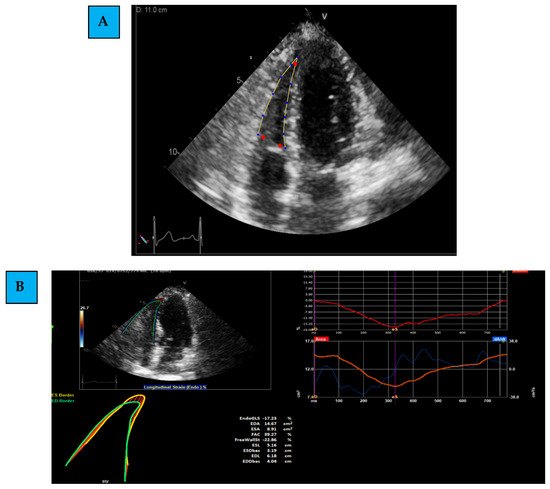

Medical history and treatment were collected from the electronic medical charts. Echocardiographic examinations were performed using the same protocol, personnel, and equipment (General Electric (GE) system, Haifa, Israel, model Vivid S70). LV echocardiographic measures included LV diameters, and LVEF [23]. TAPSE was measured as the distance of systolic excursion of the RV annular segment along its longitudinal plane, using M-mode from the apical 4C window [18]. Images were acquired using a high frame rate (>50 frames/s) [24]. LV GLS was measured using EchoPac STE software. LV boundaries were assessed at the end-systolic frame, which was first measured by automatic tracking and was later followed by performing manual corrections and optimization of images. We then performed offline measurements of RV 2D-STE by TOMTEC software, using the 2D PCA (cardiac performance analysis) application. The assessment included the following steps, as accepted by the most updated literature [25,26]: (Figure 1A–C)

Figure 1.

The assessment of right ventricle Global Longitudinal Strain. (A) Determining of the region of interest; (B) evaluating the Global Longitudinal Strain of the right ventricle; (C) evaluating the free wall by excluding the septal wall and including the RV free wall (basal, mid, and apical) segments solely.

- Evaluating Global and Regional Longitudinal Strain: RV GLS is the average of 6 segments (3 of the free wall and 3 of the septum) (Figure 1B). Each wall of the RV is divided into 3 equal parts from the base to the apex. RV FWLS PK is, for example, the average measured strain of the basal, mid, and apical segments of the RV FWLS PK solely (Figure 1C).